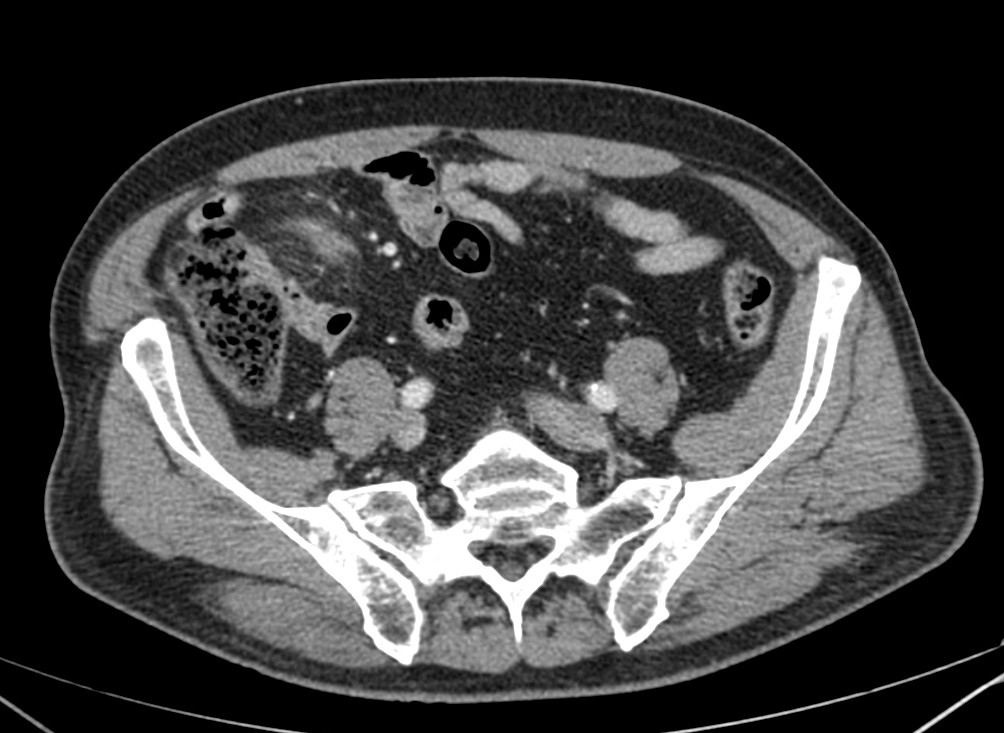

Se sospecha diverticulitis, se realiza TAC de abdomen:

Al igual que el caso anterior, nos encontramos nuevamente ante una apendagitis. Esta vez la sospecha era por diverticulitis, la anterior creíamos enfrentarnos a una apendicitis probablemente.

TAC: Imagen oval con aumento de la atenuación central, inferior a 5 cm de diámetro, contigüa al colon, con afectación de la grasa periférica. El aumento de la atenuación central es un signo de trombosis venosa muy útil para el diagnóstico, pero su ausencia no excluye en diagnóstico de apendagitis. Otros hallazgos, como aumento de la pared colónica o formación de abscesos son raros. Aunque los síntomas remiten en dos semanas, los cambios en la TAC pueden prolongarse más tiempo (pueden mantenerse, disminuir o quedar una atenuación residual), aunque en 6 mese suele haber remitido completamente. En Ecografía suele observarse en el área de máxima sensibilidad al dolor, una masa hiperecogénica, inferior a 5 cm, no compresible, adyacente al colon y sin señal Doppler.